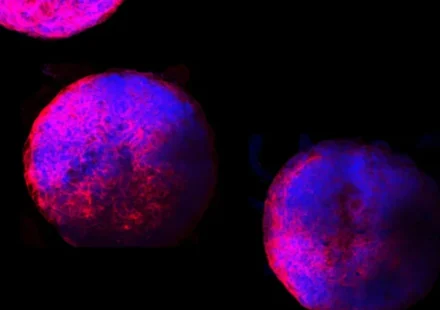

Ученые создали в лаборатории первые в мире функциональные миниатюрные человеческие сердца. Выращенные из стволовых клеток, эти «органоиды» сердца состоят из всех первичных типов клеток сердца и имеют функционирующие камеры и сосудистую сеть.…